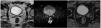

Atypical prostate cancer recurrence in the vas deferens detected by [18F]F-piflufolastat PET/CT imaging

Recidiva atípica de cáncer de próstata en conducto deferente detectado en PET/TC [18F]F-Piflufolastat